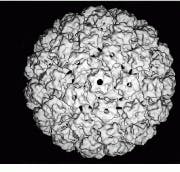

The NIH facility uses a CM 200 FEG (field-emission gun) electron microscope from FEI (Hillsboro, OR), a company now affiliated with Philips Electronics (Eindhoven, The Netherlands) through the acquisition of Philips Electron Optics, and a Zeiss (Thornwood, NY) 902 electron microscope. According to Steven, the CM 200 FEG offers the most coherent source of electrons and the highest resolutions for molecular imaging at NIH. For example, this machine has produced the highest-resolution electron micrographs (9 Å) of a protein within the Hepatitis-B virus and of bovine papillomavirus (9 Å see Fig. 2).

FIGURE 2. Using a CM 200 FEG (field- emission gun) electron microscope from FEI (Hillsboro, OR), NIH researchers have produced 9-Å electron micrographs of bovine papillomavirus.